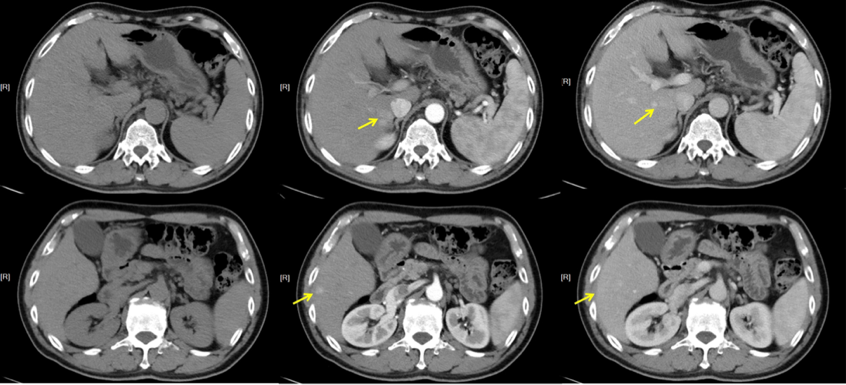

彭某,男性,58岁。2015-07在我院体检时胸部+腹部增强CT提示肝癌,肺部无转移。

影像学检查:2020-05门诊CT:

影像提示:碘油CT